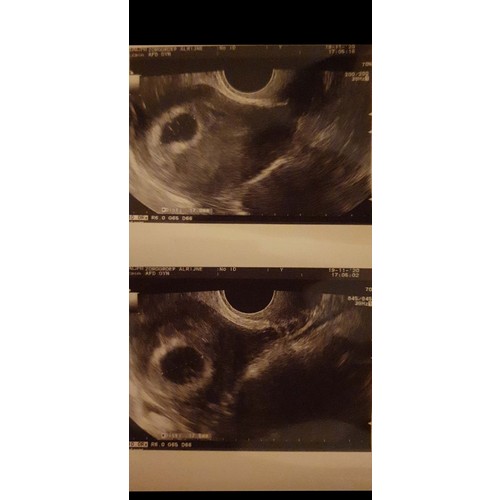

Dit was mijn tweeling echo op 5w5, gaat nog allemaal prima. Morgen 19 weken馃グ

Dit was mijn tweeling echo op 5w5, gaat nog allemaal prima. Morgen 19 weken ...